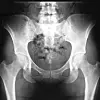

Ved å koble opplysninger fra helseundersøkelser, biobanker og nasjonale registre vil forskerne finne årsaken til at Norge har så mange hoftebrudd. Foto: Shutterstock

Norge ligger i verdenstoppen når det gjelder hoftebrudd, og ingen vet hvorfor.

Brudd i hoften er et stort folkehelseproblem, som koster samfunnet store penger i form av sykehusinnleggelse, operasjoner og sykefravær.

Det er ofte smertefullt, mange blir invalide over lengre tid, og hoftebrudd kan føre til økt dødelighet. Nå vil forskerne finne årsakene.